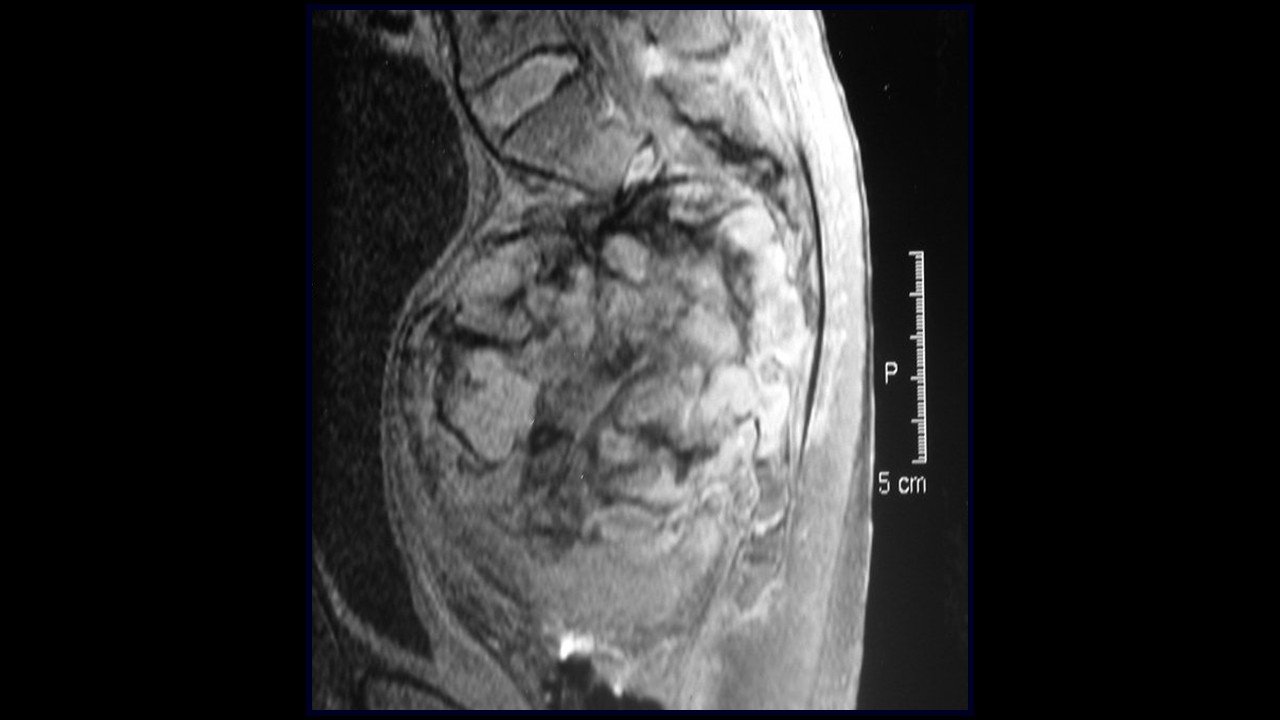

Nesta segunda parte da conferência sobre a sacrectomia total sem reconstrução, apresentaremos a utilização das serras de Gigli, que agora são posicionadas por um novo acesso: a videolaparoscopia!